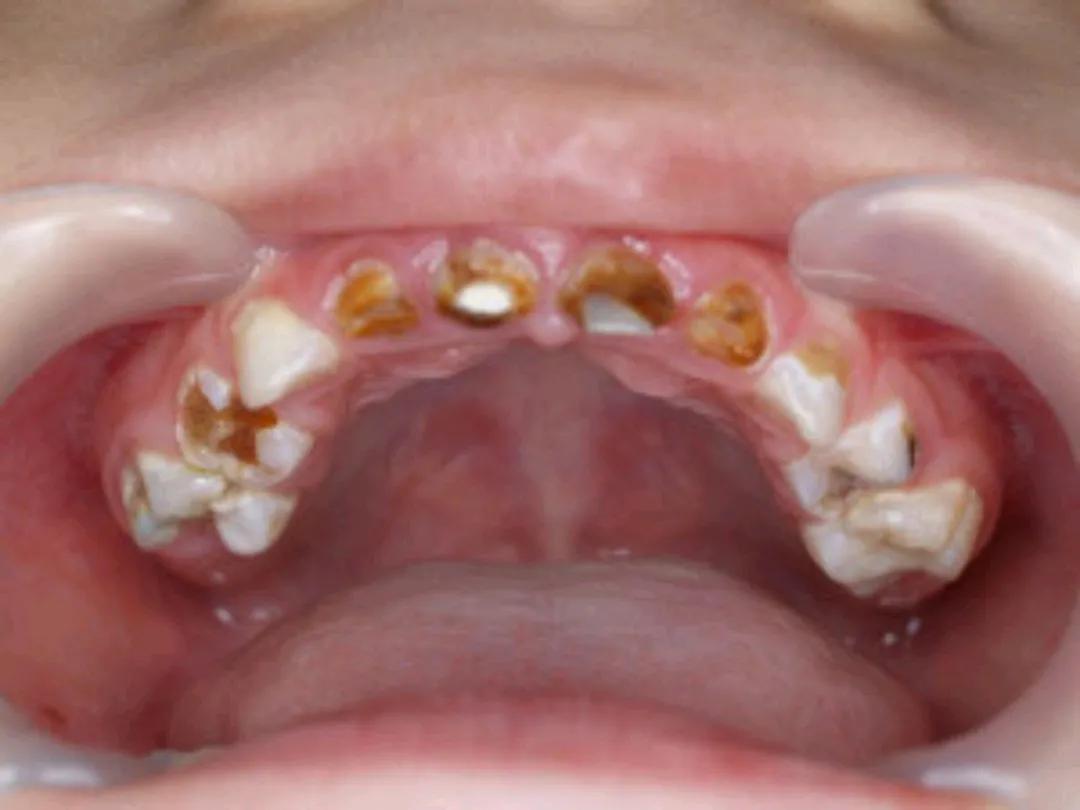

除了前面谈到的全麻下拔牙,小孩子补牙也可以在全麻下进行。因为,小孩子配合程度差,口腔卫生情况不理想者,很多都是满口牙齿龋坏,甚至牙龈鼓包、松动等现象;而且常规的乳牙根管治疗一颗牙就需要3-5次,就诊时间长,治疗过程中也会有不同程度的不适。诸多原因使得小孩子在门诊处理口腔问题带来了困难。

因此,针对全口多发龋齿且不配合的患儿,都可以考虑在全麻手术下一次性完成相关治疗,既省时也减轻患儿的痛苦体验,这称之为舒适化治疗,目前在国内很多三甲医院都已经开展。